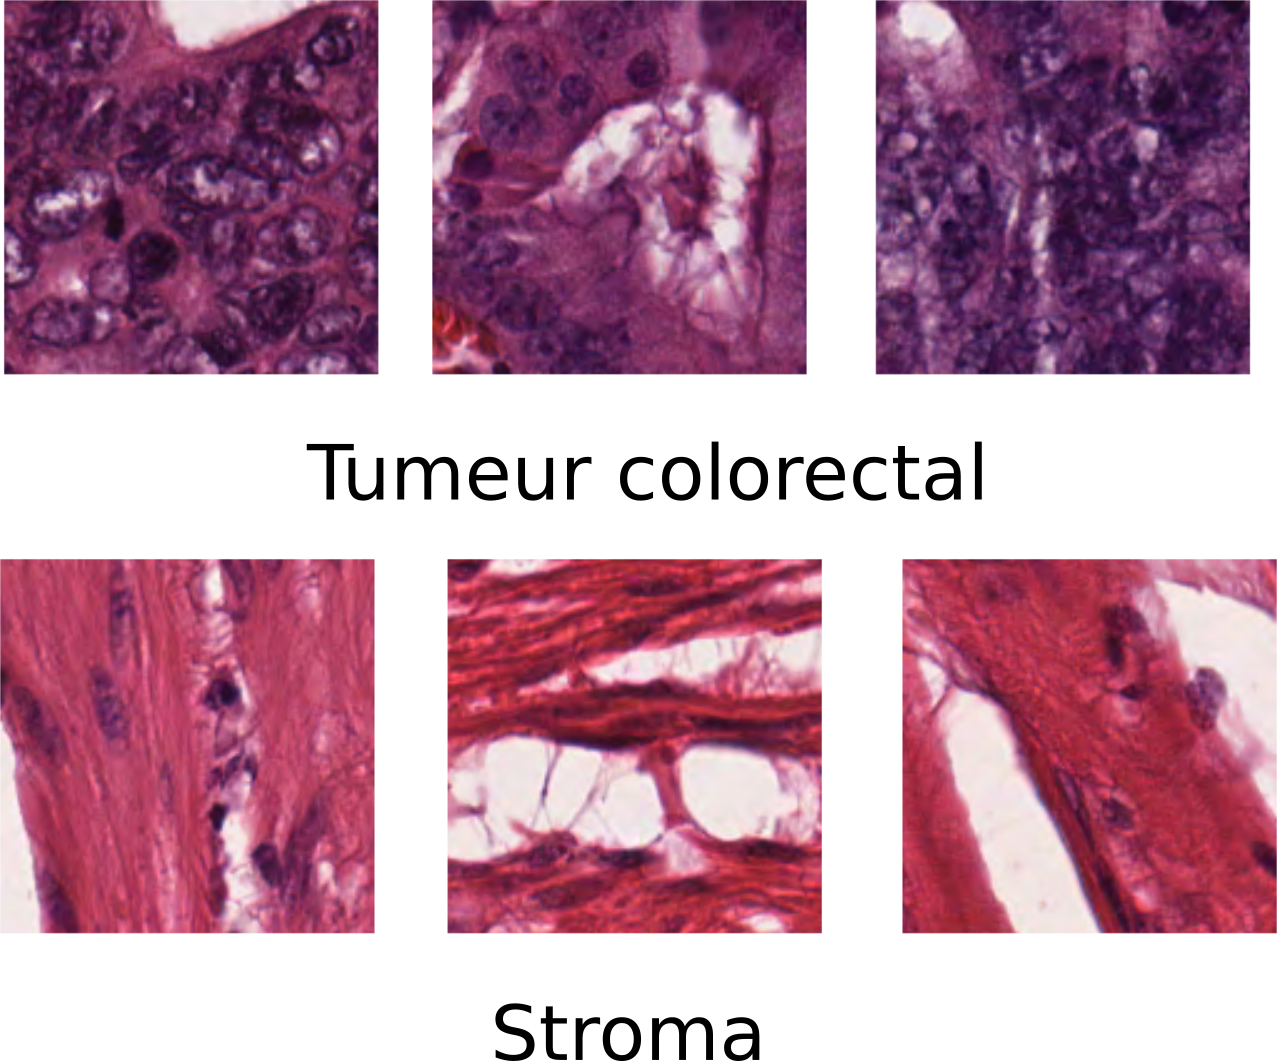

Pour diagnostiquer le cancer, les médecins utilisent l’analyse histopathologique, celle-ci consiste à prélever un tissu malade sur le patient (biopsie) et à l’observé au microscope afin de détecter et de quantifier les cellules cancéreuses. Il est très important lors des stades précoces du cancer de savoir distinguer les cellules cancéreuses des cellules saines.

Lors de l’examen de l’échantillon sous le microscope, le pathologiste cherchera notamment la présence d'anomalies dans la structure des cellules où des changements dans la distribution de ces dernières. Ce diagnostic est très subjectif, car pour l’effectuer le médecin se repose principalement sur son expérience et donc cela mène à une énorme variabilité de l’analyse d’un pathologiste à l'autre. C’est pourquoi afin de normaliser ce processus d’analyse, il est important d’automatiser le diagnostic du cancer à l’aide d’outils logiciels capables de réaliser des mesures quantitatives permettant ainsi au médecin d’avoir un jugement objectif de la situation du patient.

La segmentation est l’étape durant laquelle les objets d’intérêt sont détectés puis extraits de l’image. Dans le cas ci-dessus la segmentation a simplement découpé l’image du tissue qui à l’origine mesurait 5000*5000 pixels a été découpé en sous-image de 50 x 50 pixels. Le but de cette segmentation est probablement de savoir avec précision jusqu’ou le tissu a été infecté par la tumeur.

Les objets précédemment extraits de l’image sont analysés afin d’en retirer des mesures pertinentes descriptives du problème à traiter. Dans le problème ci-dessus, les informations qui seront extraites seront des informations de texture et de couleurs. Car l’on peut remarquer que la texture et la couleur de l’échantillon changent selon que la zone traitée soit infectée ou pas.

La classification permettra de savoir à partir des informations précédemment extraites si la zone traitée est affectée où non.